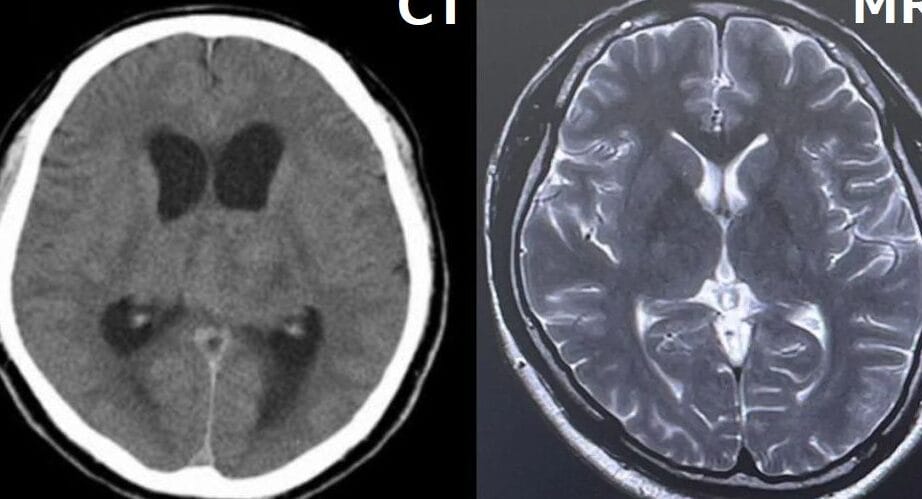

CT(コンピュータ断層撮影)とMRI(磁気共鳴画像法)は、現代の医療において非常に重要な画像診断技術です。それぞれ異なる原理で身体内部の様子を可視化しますが、その特性や用途に大きな違いがあります。ユーザーがこの二つの技術について知りたいと思う背景には、病気の診断や治療方針を決定するための情報収集があるでしょう。具体的には、CTは短時間で得られる高精細な画像によって、骨折や内出血などの急性の問題を迅速に評価するのに適しています。一方、MRIは軟部組織の詳細な画像を提供し、腫瘍や神経系の障害などの慢性疾患の診断に向いています。

医学の分野では、画像診断は非常に重要な役割を果たしています。その中でも、コンピューター断層撮影(CT)と磁気共鳴画像法(MRI)は、最も一般的に使用される二つの手法です。これらはそれぞれ異なる技術と特性を持っており、診断における適応が異なります。以下では、CTとMRIのそれぞれの特性、利点、欠点を比較し、理解を深めます。

- 撮影手法:CTはX線を使用し、MRIは磁気とラジオ波を使用します。

- 解像度:CTは硬組織に強く、MRIは軟部組織に優れています。

- 被曝リスク:CTは放射線を用いるため、被曝の懸念がある。一方、MRIは放射線を使用しません。

| 画像の解像度 | 硬組織に強い | 軟部組織に優れる |